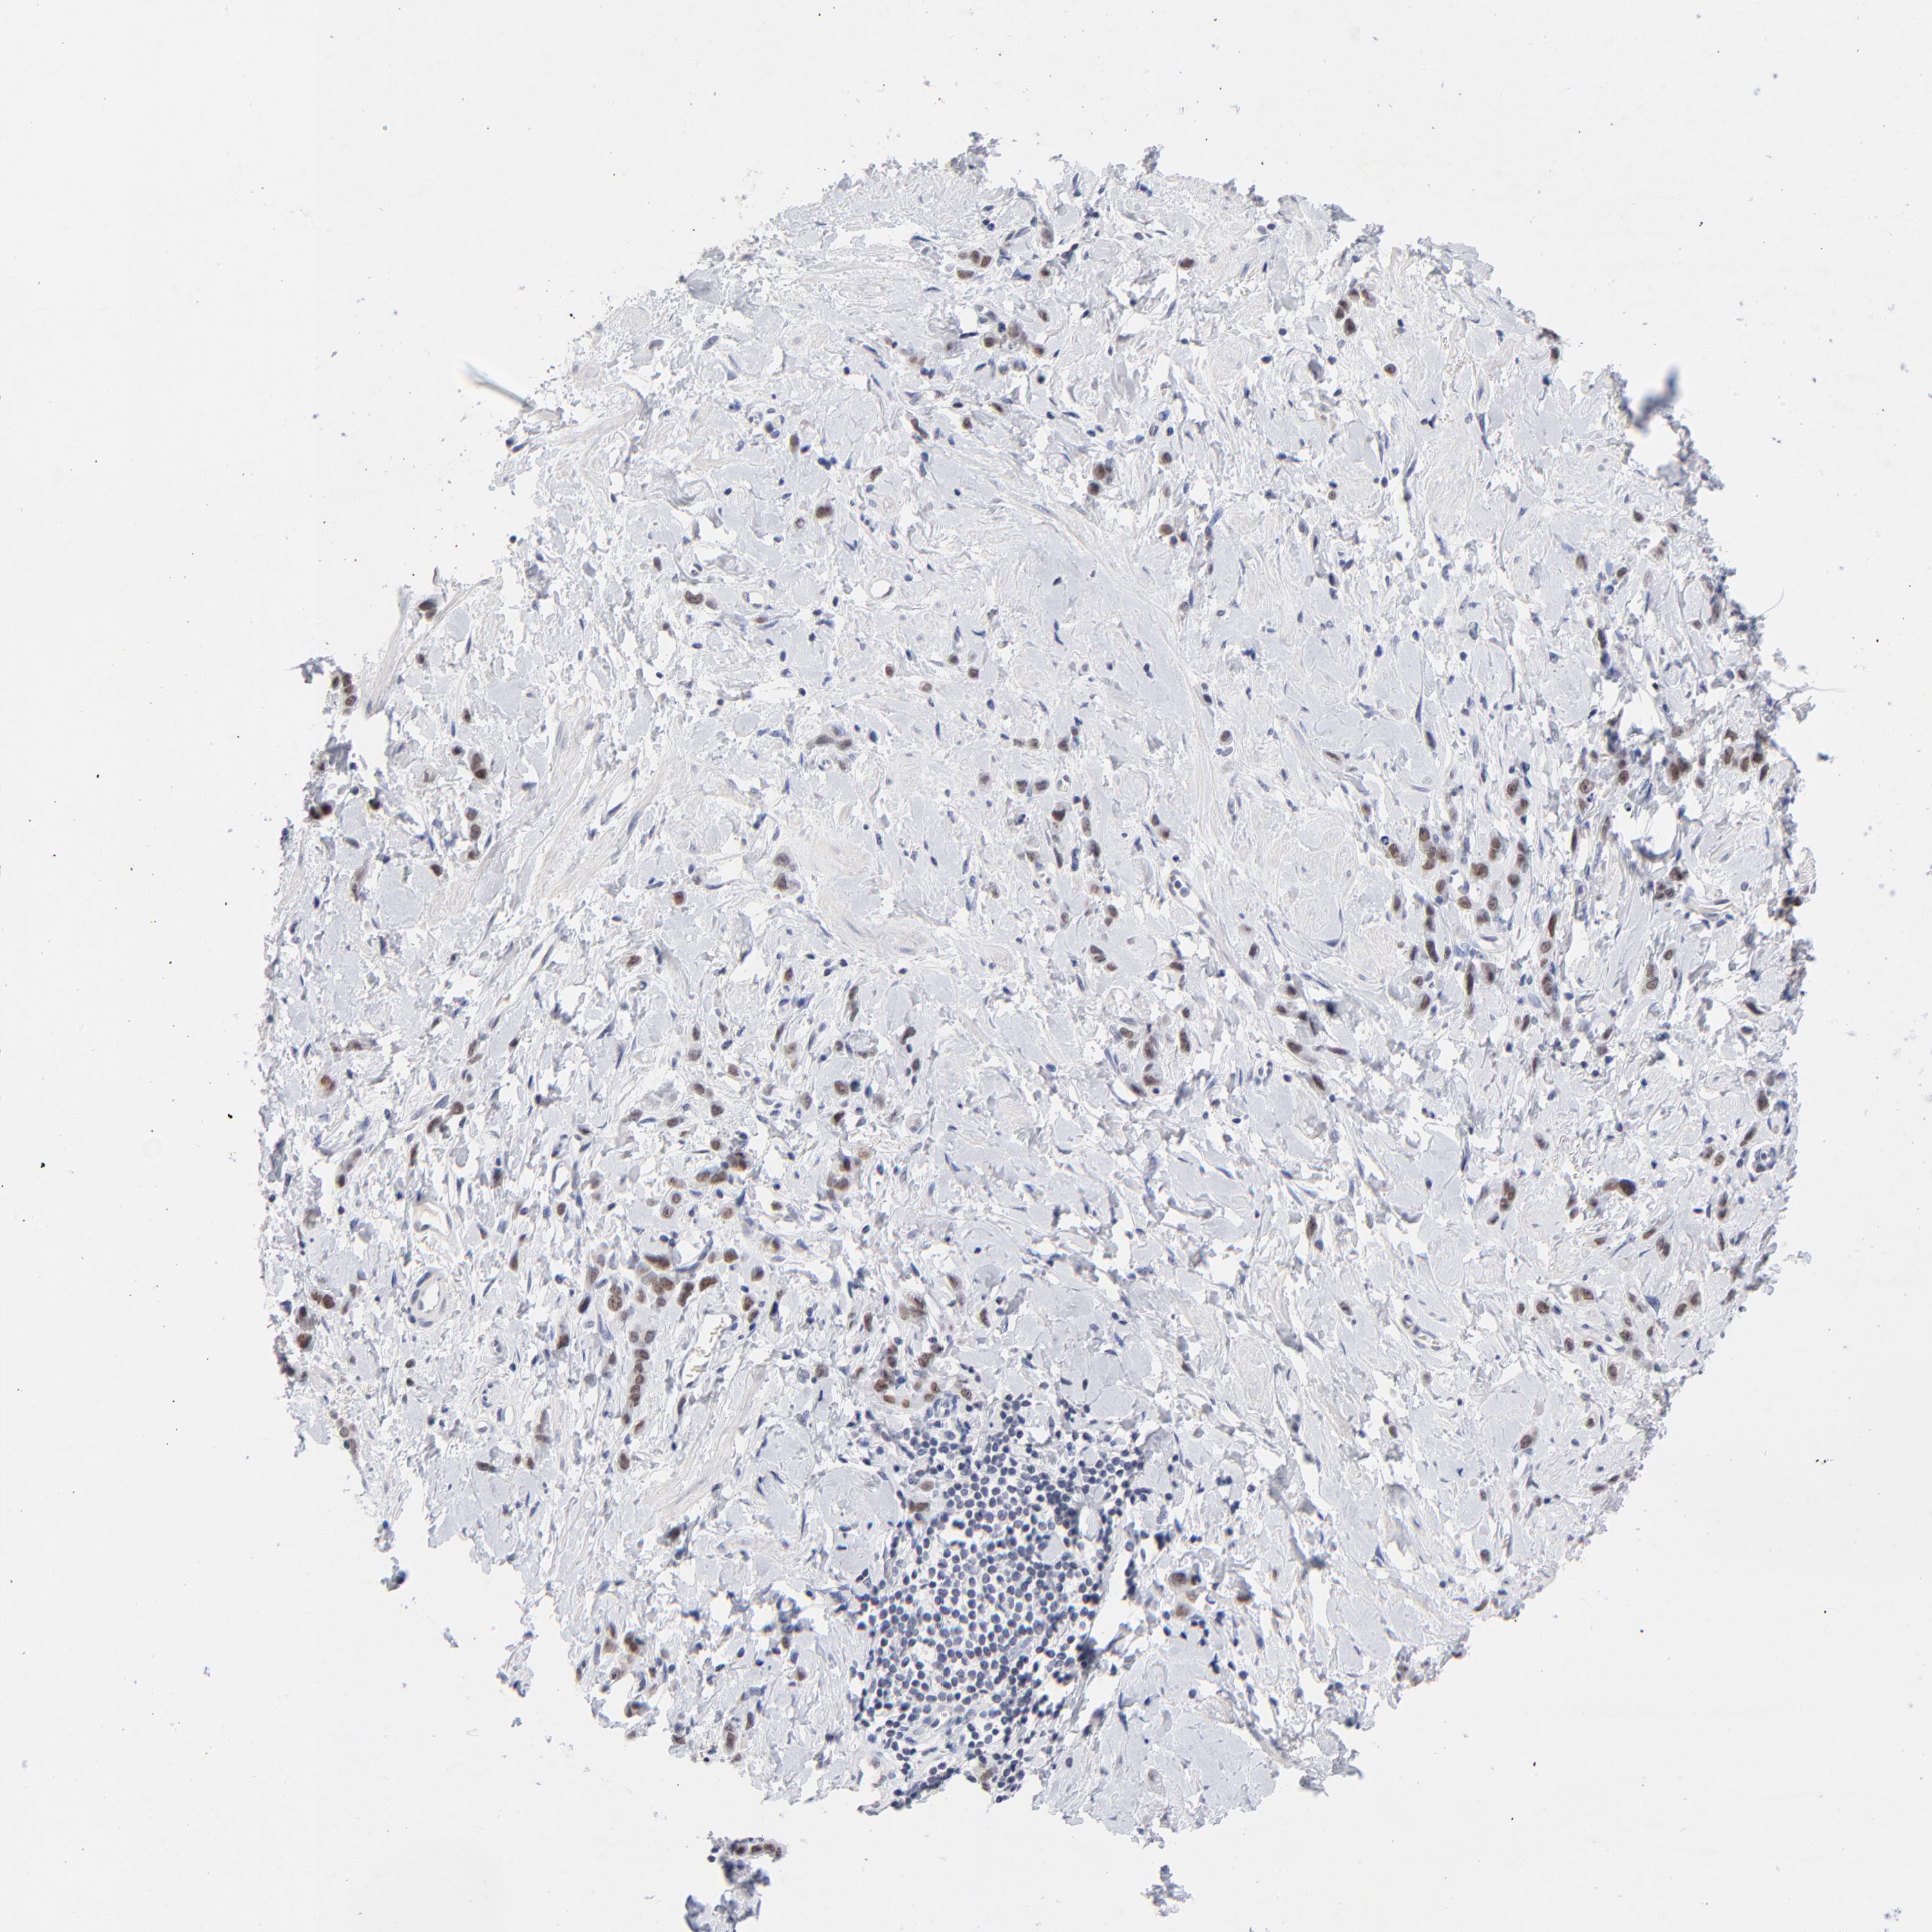

STOMACH CANCER - Protein expressioni

A mouse-over function shows sample information and annotation data. Click on an image to view it in a full screen mode. Samples can be filtered based on level of antibody staining by selecting one or several of the following categories: high, medium, low and not detected. The assay and annotation is described here.

Note that samples used for immunohistochemistry by the Human Protein Atlas do not correspond to samples in the TCGA dataset.

Antibody stainingi

Antibody staining in the annotated cell types in the current human tissue is reported as not detected, low, medium, or high, based on conventional immunohistochemistry profiling in selected tissues. This score is based on the combination of the staining intensity and fraction of stained cells.

Each image is clickable and will lead to virtual microscopy that enables deeper exploration of all samples and also displays staining intensity scores, fraction scores and subcellular localization as well as patient and tissue information for each sample.

Antibody CAB003693

Staining

High

Medium

Low

Not detected

Intensity

Strong

Moderate

Weak

Negative

Quantity

>75%

75%-25%

<25%

None

Location

Nuclear

Cytoplasmic/membranous

Cytoplasmic/membranous,nuclear

Adenocarcinoma, NOS

Adenocarcinoma, High grade